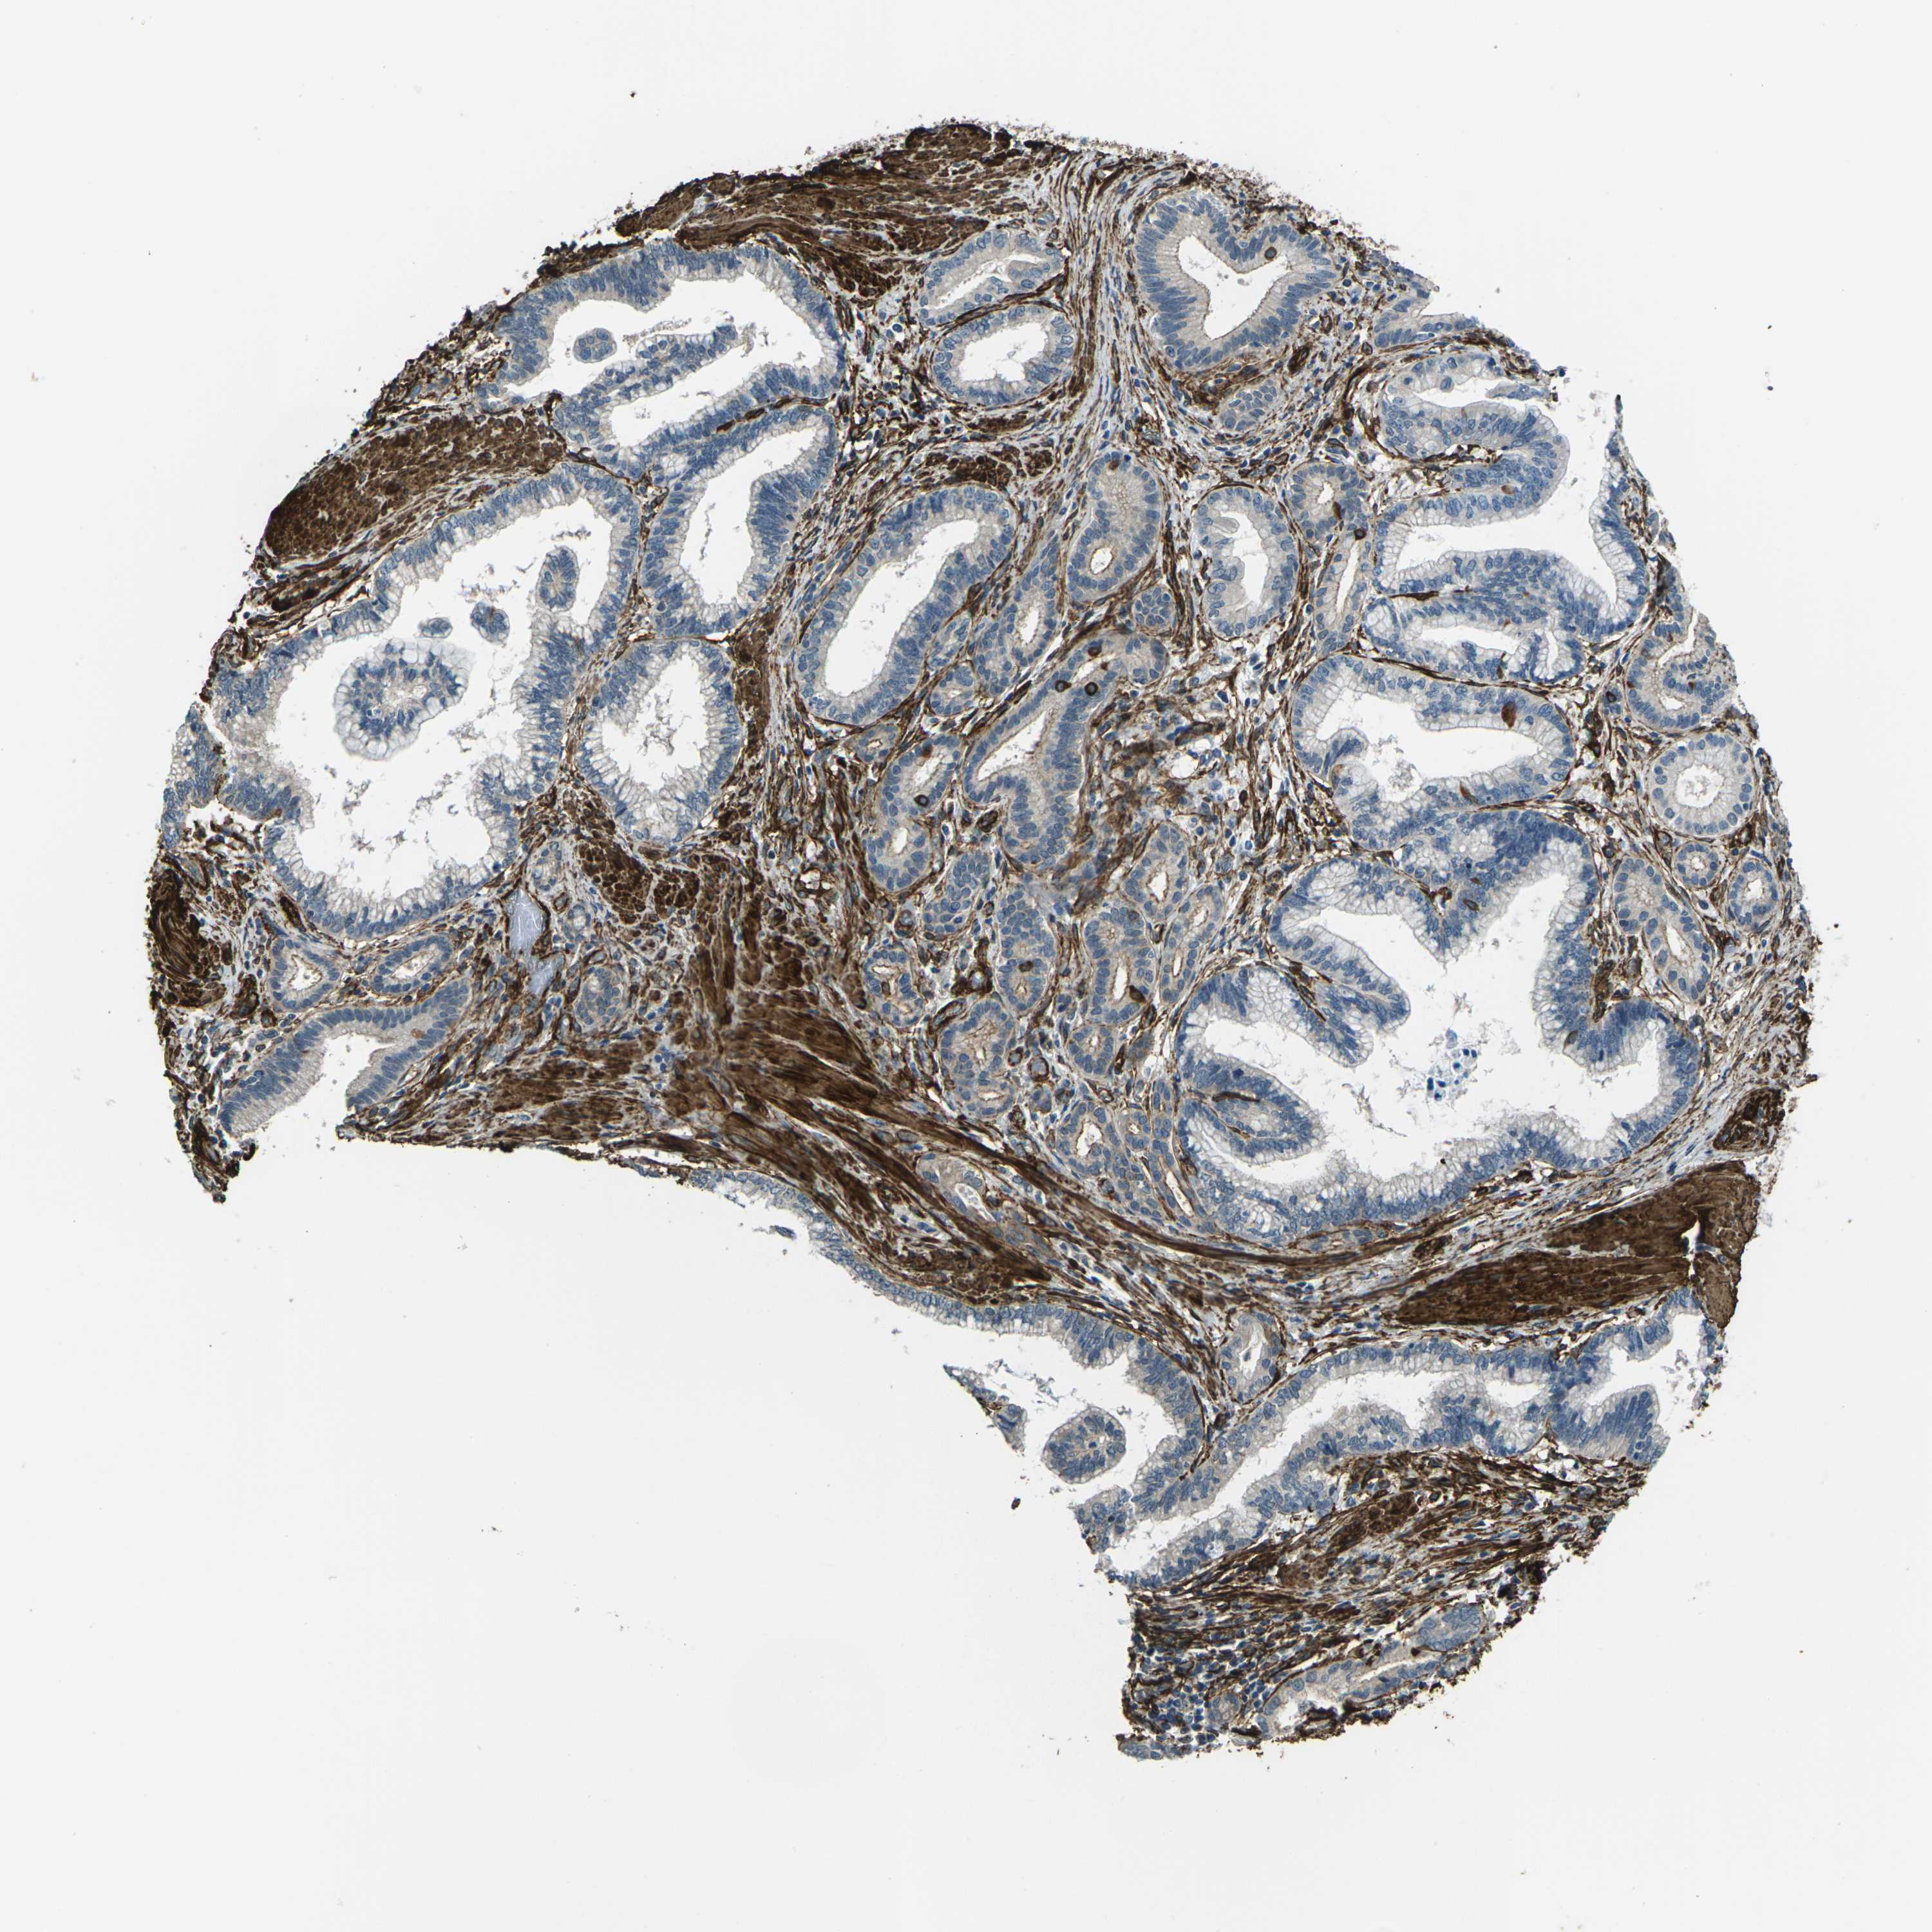

PANCREATIC CANCER - Protein expressioni

A mouse-over function shows sample information and annotation data. Click on an image to view it in a full screen mode. Samples can be filtered based on level of antibody staining by selecting one or several of the following categories: high, medium, low and not detected. The assay and annotation is described here.

Note that samples used for immunohistochemistry by the Human Protein Atlas do not correspond to samples in the TCGA dataset.

Antibody stainingi

Antibody staining in the annotated cell types in the current human tissue is reported as not detected, low, medium, or high, based on conventional immunohistochemistry profiling in selected tissues. This score is based on the combination of the staining intensity and fraction of stained cells.

Each image is clickable and will lead to virtual microscopy that enables deeper exploration of all samples and also displays staining intensity scores, fraction scores and subcellular localization as well as patient and tissue information for each sample.

Antibody HPA012316

Staining

High

Medium

Low

Not detected

Intensity

Strong

Moderate

Weak

Negative

Quantity

>75%

75%-25%

<25%

None

Location

Nuclear

Cytoplasmic/membranous

Cytoplasmic/membranous,nuclear

Adenocarcinoma, NOS

Adenocarcinoma, metastatic, NOS